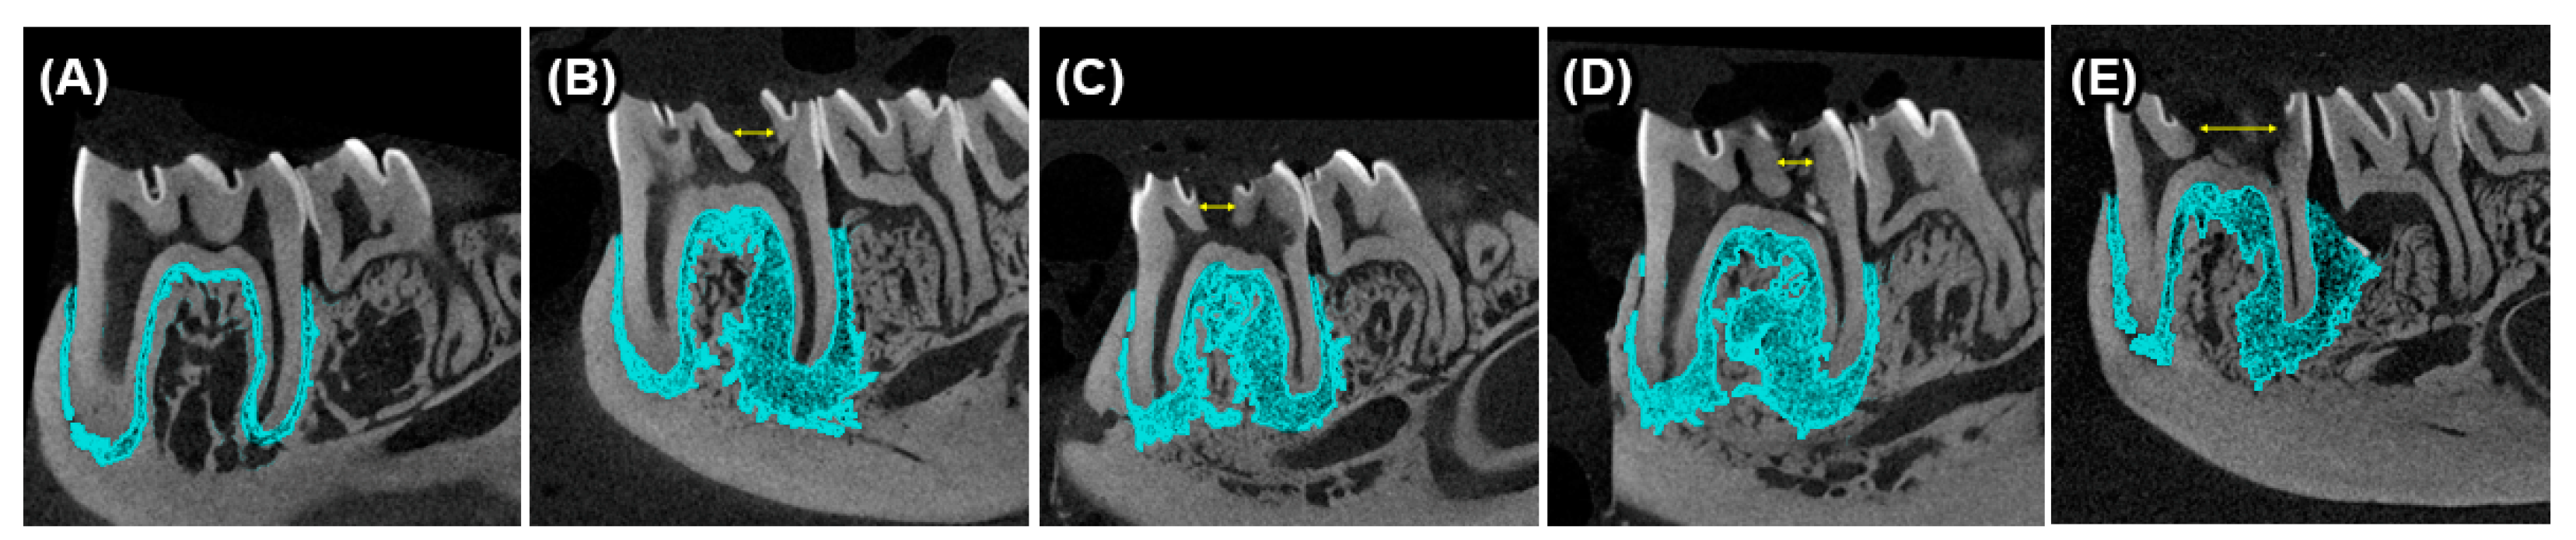

4.3. Apical Periodontitis Induction

4.4. Sample Collection and Histological Processing

4.5. Histomorphometric Analyses